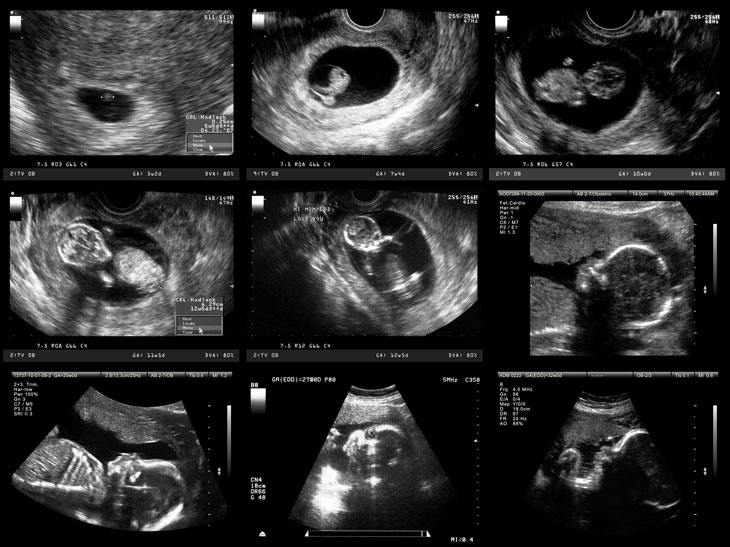

Hình ảnh siêu âm cho thấy sự phát triển của thai nhi

Siêu âm sẽ thấy được hình thái thai nhi này nhằm kiểm tra các bất thường về cấu trúc, vị trí của bánh nhau và các ngôi thai đa thai. Điều thú vị là có thể quan sát thấy hiện tượng nấc cụt ở thai nhi.